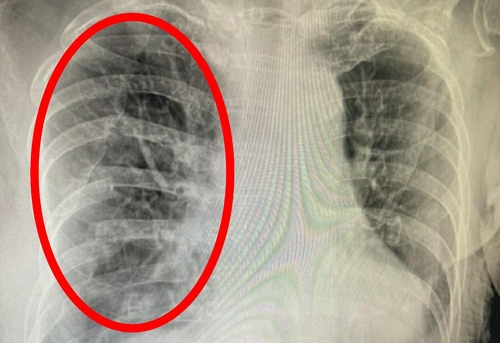

오른쪽 갈비뼈 아래 통증 원인 - 폐렴/폐암 등 폐 질환

숨 쉴 때 곤란함과 갈비뼈, 가슴의 압박감, 답답함 등은 물론 잦은 기침, 쌕쌕거리는 숨소리 등이 있다고 한다면 폐 질환을 생각해 보아야 하는데 엑스레이 등으로 폐의 컨디션을 체크해 보는 것이 중요 해요 특히나체중의 감소와 같이 과도한 기침이 3주 이상 진행되었을 경우이라면 폐결핵, 기흉, 폐암 등을 확인해 볼 필요가 있어요.